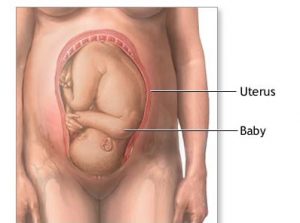

O sistema nervoso do bebê está totalmente formado, assim como seu sistema imunológico. Seus pulmões já estão praticamente desenvolvidos e, se nascer nesta semana, tem grandes chances de conseguir respirar normalmente após o parto. Cada dia mais seu bebê estará preparado para vir ao mundo e encaixando cada vez mais na sua bacia. Você notará sua barriga descendo com o passar dessas 34 semanas de gravidez.